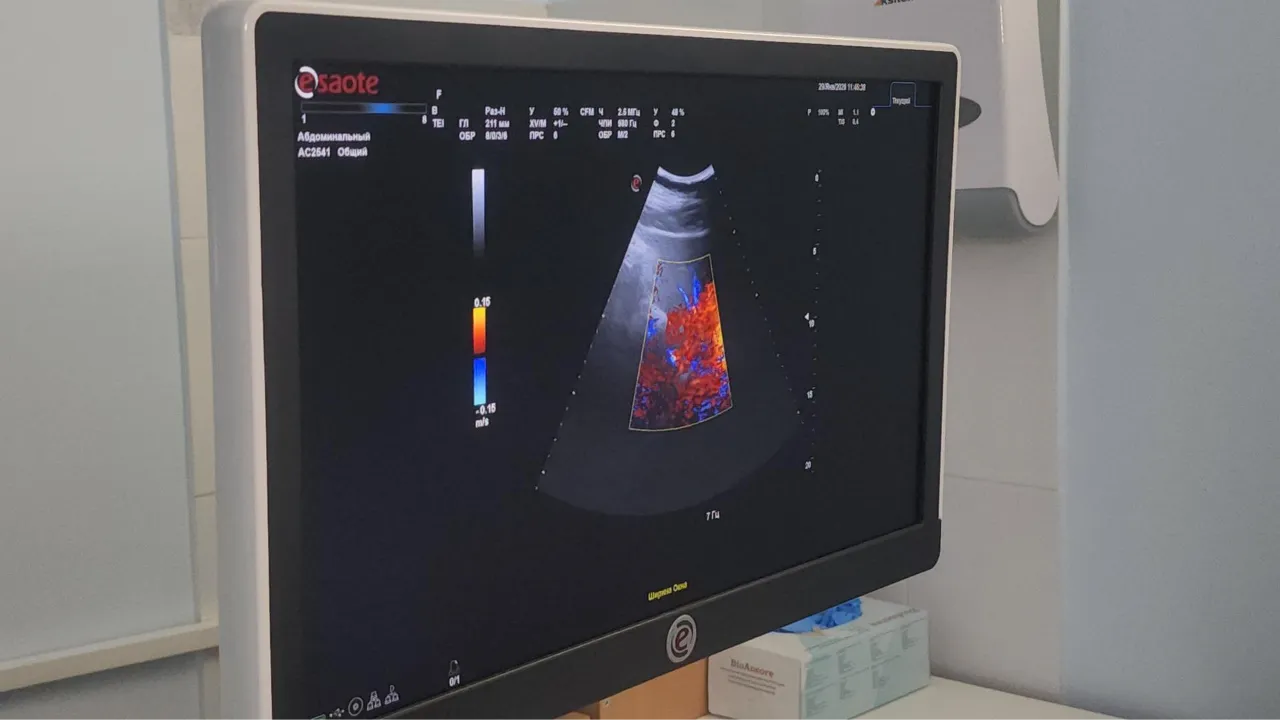

Для обследования в маммологическом центре используют весь профиль современной диагностики — это и маммография, и УЗИ экспертного класса.